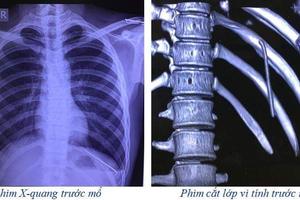

(Thanh tra)- Ngày 30/5, thông tin từ Đơn vị Phẫu thuật Tim mạch - Lồng ngực (Bệnh viện Đa khoa tỉnh Phú Thọ) cho biết: Các bác sĩ vừa thực hiện thành công một ca bệnh hy hữu. Chiếc đinh tự động di chuyển từ vai rơi xuống khoang màng phổi một thanh niên 18 tuổi.